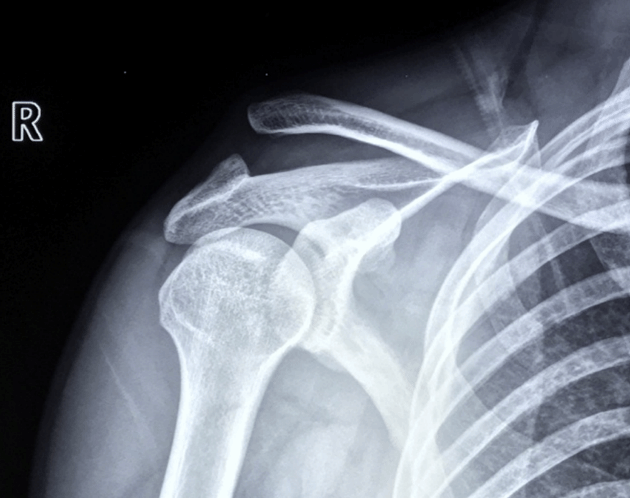

肩关节Bony-Bankart损伤

肩关节镜下缝合修复Bony-Bankart术后